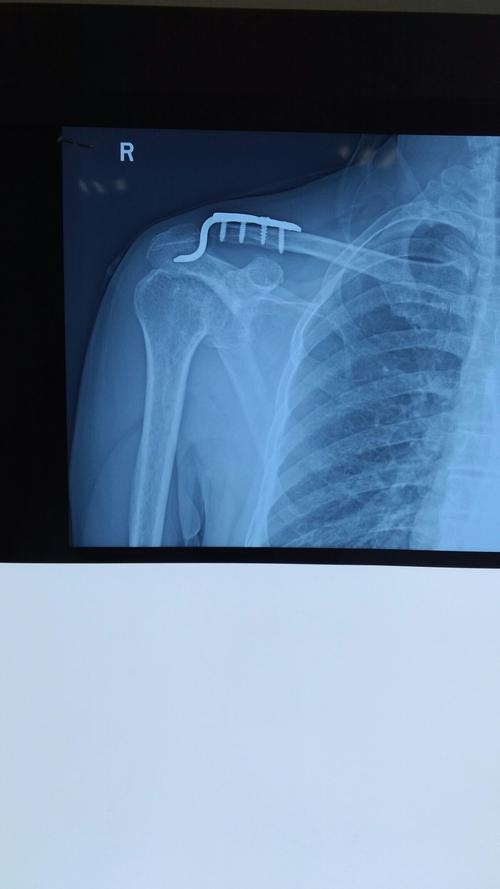

肩锁关节脱位关节镜微创复位固定

肩锁关节脱位术前术后

微创小切口解决肩锁关节脱位

肩锁关节脱位手术

肩锁关节脱位手术图解

肩锁关节脱位